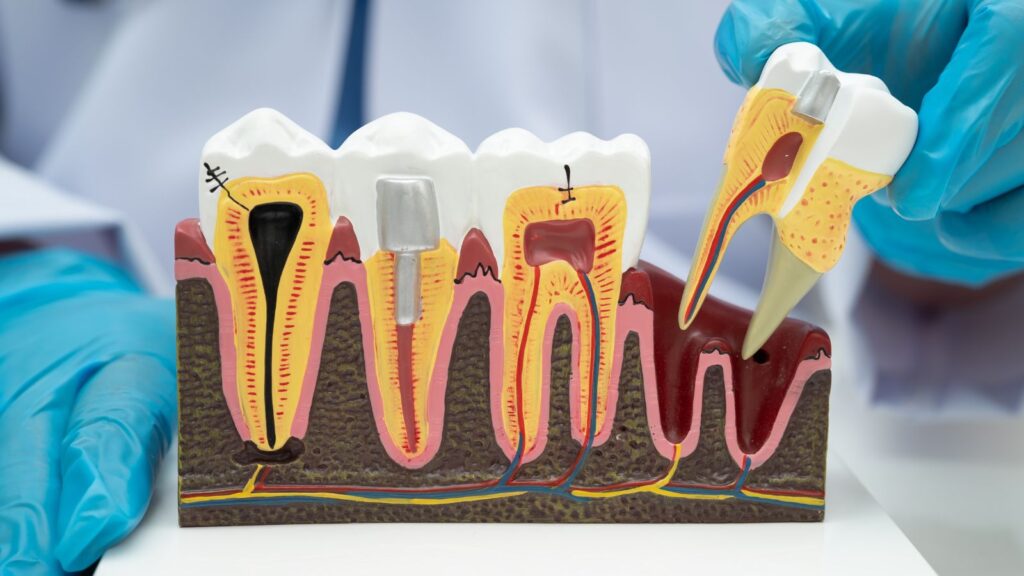

Dental Implants

Dental implants replace tooth roots with titanium posts placed into jawbone. You get a single crown, a bridge, or a full-arch prosthesis anchored to those posts. Implants fuse to bone (osseointegration), which keeps them stable and helps prevent bone loss.

Expect several visits over months. Your dentist will assess bone volume, sometimes add bone grafts, then place the implant and later attach the abutment and crown. Implants need daily cleaning like natural teeth. They often last decades with good care but cost more up front than other options.

Fixed Dental Bridges

A fixed bridge fills a gap by bonding a false tooth (pontic) to adjacent teeth or implant crowns. You keep normal chewing function without surgery if you use natural teeth as supports. Bridges work well when nearby teeth are strong or when implants are not possible.

Preparation requires reshaping the supporting teeth to fit crowns. You will get temporary restorations while the lab makes the bridge. Bridges last 5–15 years on average and need careful flossing under the pontic to prevent decay and gum problems. Repair or replacement occurs if supporting teeth fail.